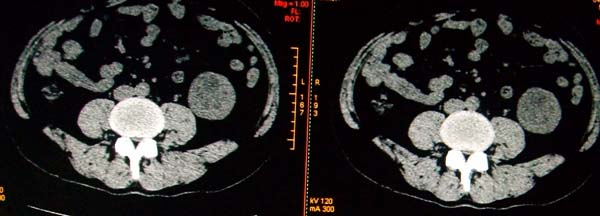

标题: CT17174:M38Y,体检超声提示右肾发育不良,病人无明显不适 [打印本页]

标题: CT17174:M38Y,体检超声提示右肾发育不良,病人无明显不适

1)左肾下极占位性病变,不排除肾癌可能;建议行进一步检查。2)右肾发育不良。

左肾下极占位性病变,不排除肾癌可能;建议增强及明确内部组织ct值。右肾发育不良。

右肾发育不良。左肾下极占位。

右肾发育不良。左肾代偿。左肾下极占位,性质待定,建议强化。

右肾发育不良。左肾下极占位。建议增强!

右肾发育不良。左肾下极囊实性占位,建议增强。